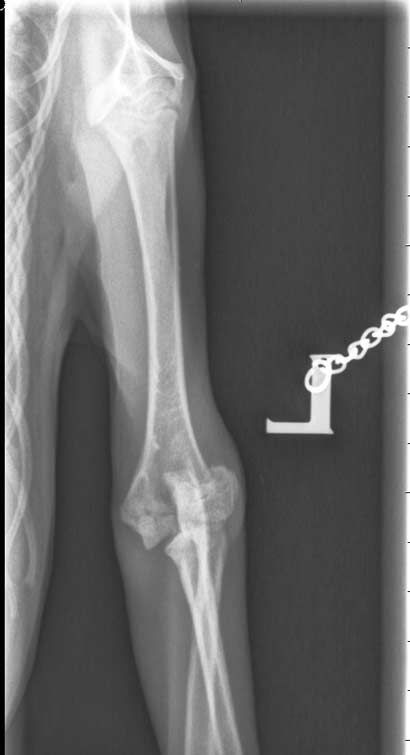

Von Looping können wir nur Gutes berichten.

Seine Brüche heilen weiterhin sehr gut und der behandelnder Arzt hat ihm erlaubt, dass er in 10 Tagen wieder uneingeschränkt Klettern und Springen darf.

Der kleine Looping war in der Tierklinik zur Röntgenkontrolle und dabei wurden auch gleich die Fäden gezogen.

Seine Frakturen heilen gut zusammen - was bei jungen Tieren ja glücklicherweise rascher geht - und Looping darf bereits in zwei Wochen schon wieder mit Artgenossen springen und rennen.